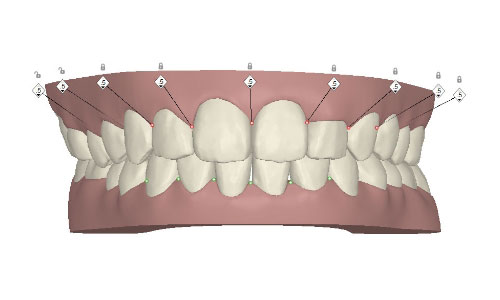

コンピューターを使って作製した透明なマウスピース型の矯正装置(アライナー)を段階的につけ替えていき、それにより歯列を矯正し、歯並びへと改善します。はじめに 治療開始から終了までのアライナーができあがってきます。マウスピース型矯正装置(インビザライン)の最大の特徴として「クリンチェック」というソフトがあります。3D のコンピュータ シュミレーション画像で、治療開始から完了までを目で見て確認することができます。

マウスピース型矯正装置(インビザライン)治療においては、クリンチェックというシミュレーションソフトを活用しております。

このクリンチェックの魅力は、治療前の現在の歯並びから治療後の歯並びを視覚化して患者様にご説明できる点にあります。

また、抜歯・非抜歯、全体矯正・部分矯正などそれぞれの治療パターンをシミュレーションすることが可能です。

| 治療前 |  |

| ライトプラン 隣接面削合なし |

|

|

| ライトプラン 隣接面削合あり |

|

|

| フルプラン 隣接面削合あり |

|

|